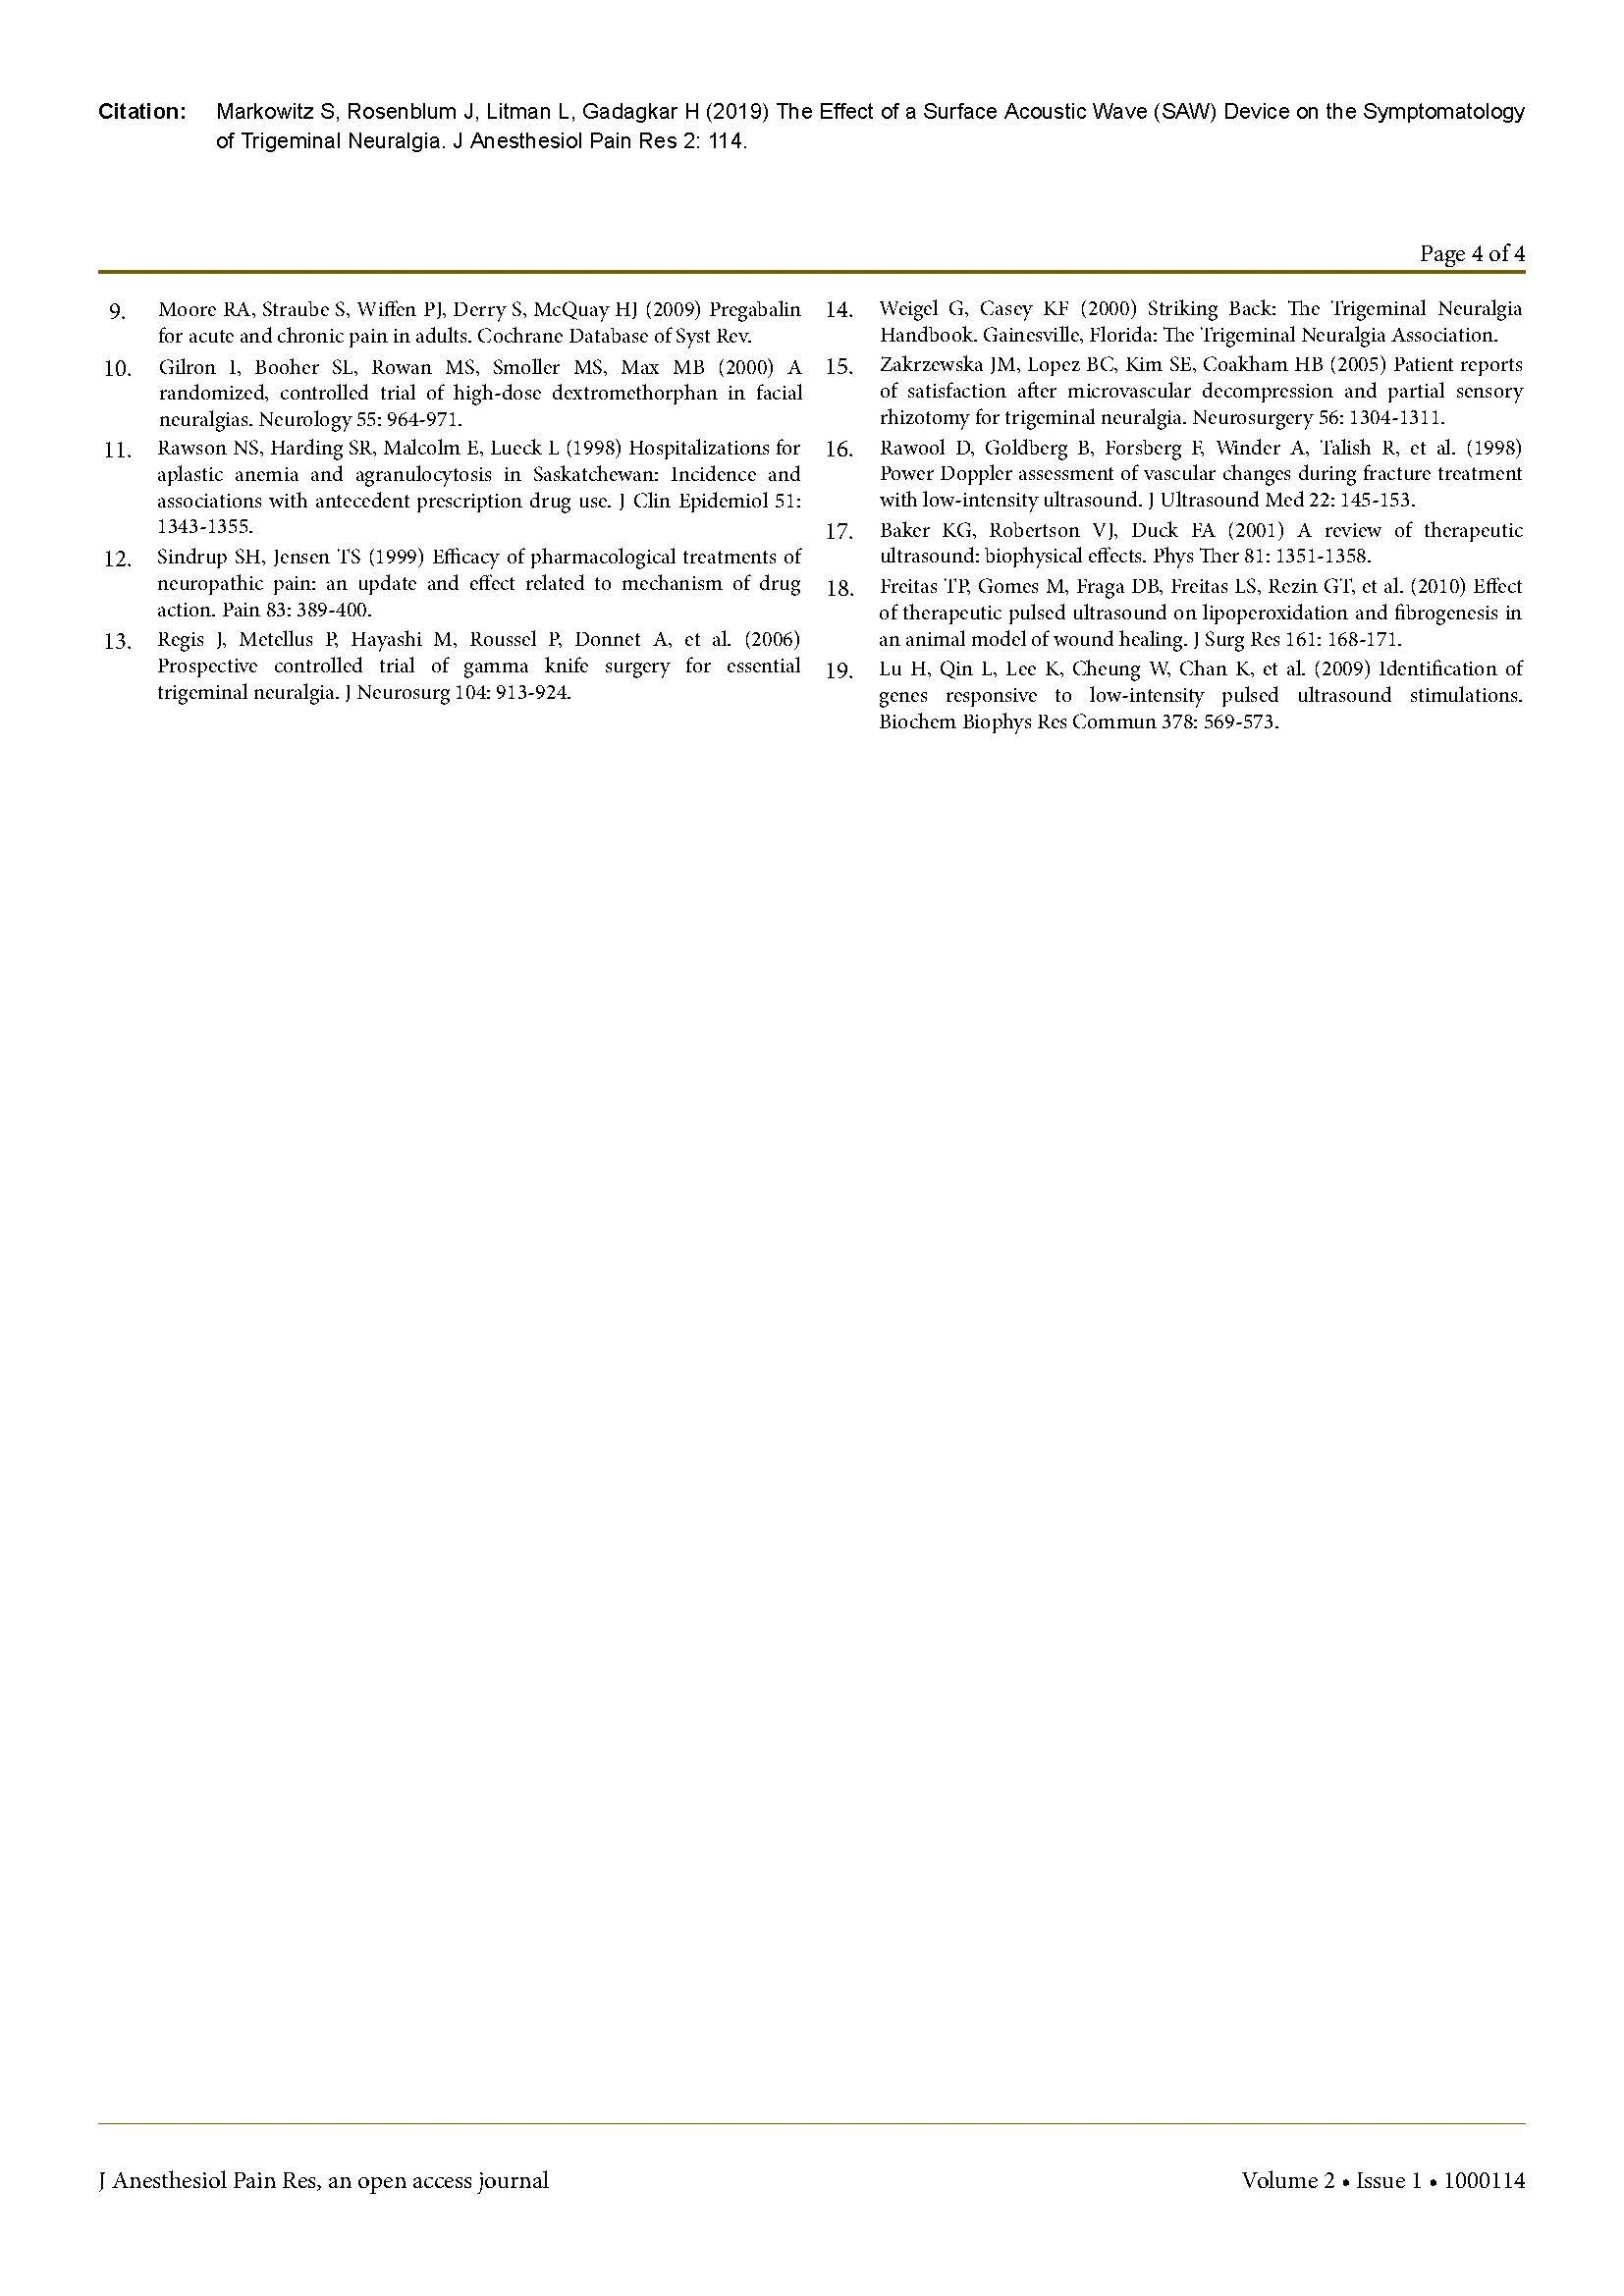

PainShield MD in the Treatment of Trigeminal Neuralgia.

A Historically Difficult to Treat Condition

Clinically Significant Pain Reduction as Measured by VAS 0-10. (1st generation device shown)